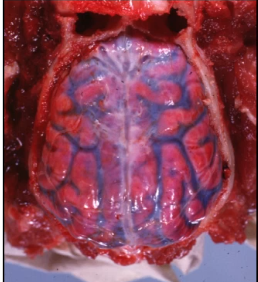

what type of hemorrhage is this?

subdural hemorrhage, which occurs between the dura mater and the brain.